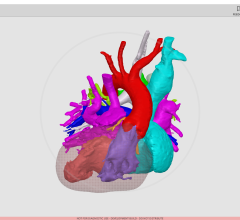

Still, 3-D printing has proven to be a powerful and useful tool, specifically in patient education, pre-surgical planning, oncology, implantable devices and more.

WhiteClouds’ patent pending "Hinge and Slice" proprietary designed models are used in complex surgeries across the nation, providing granular, detailed patient-specific models. Jay Bishoff, M.D., urologic surgeon and director of the Intermountain Urological Institute for Intermountain Healthcare, stated, “Having performed over a thousand procedures, I am confident that 3-D models can play a role in helping good surgeons become great. “

WhiteClouds also announced the launch of 3DyourSCAN, a life-size color printed, anatomical model of a patient's computed tomography (CT) or magnetic resonance imaging (MRI) scan designed to improve collaboration and education between physicians and patients.